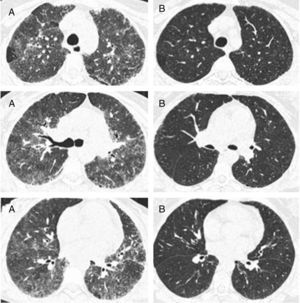

In the nine patients with a second HRCT scan, after a period treatment with corticosteroids and DMARDs of one to two years, a tendency of lowering in ground-glass score was observed (median [IQR]): (2.33 [2,3] vs. 2 [1.33–2.16]), P<0.056, along with lowering in CDAI score (27 [8–43] vs. 9 [5–12]), P<0.063 (Fig. 2).

Representative images of HRCT scan after and before treatment with prednisone and DMARDs. (A) Basal HRCT images, showing bilateral ground-glass images, centroliobular nodules and lobular areas of decreased attenuation. (B) There is a general improvement of the ground glass and no images of centroliobular nodules and lobular areas of decreased attenuation. The patient was treated with prednisone, methotrexate and sulphasalazine. There is a difference of 16 months between basal HRCT (A) and follow-up HRCT (B).